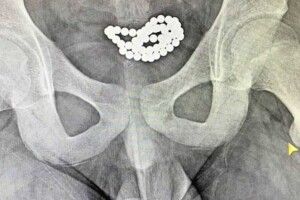

Інтимні експерименти: на Волині підлітки запхали в уретру магнітні кульки і потрапили в лікарню Медицина 09.02.2022, 13:55